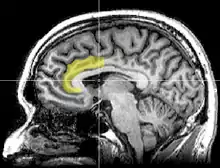

Córtex cingulado anterior

No cérebro humano, o córtex cingulado anterior (CCA) é a parte frontal do córtex cingulado que se assemelha a um "colar" ao redor da parte frontal do corpo caloso. É composto pelas áreas 24, 32 e 33 de Brodmann.

O córtex cingulado anterior pode ser dividido anatomicamente com base nos componentes cognitivo (dorsal) e emocional (ventral).[7] A parte dorsal do ACC é conectada ao córtex pré-frontal e córtex parietal, bem como ao sistema motor e aos campos oculares frontais,[8] tornando-o uma estação central para processar estímulos de cima para baixo e de baixo para cima e atribuir controle apropriado para outras áreas do cérebro. Por outro lado, a parte ventral do ACC está conectada à amígdala, núcleo accumbens, hipotálamo, hipocampo e ínsula anterior, e está envolvida na avaliação da importância da emoção e das informações motivacionais. O ACC parece estar especialmente envolvido quando são necessários esforços para realizar uma tarefa, como na aprendizagem precoce e na solução de problemas.[9]